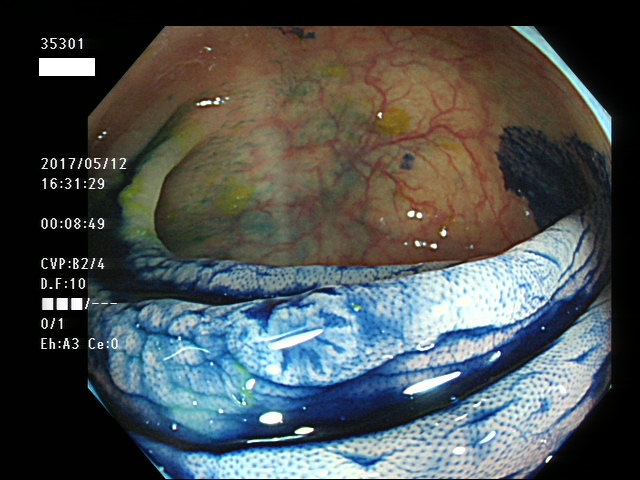

上記100名より抽出した平坦・陥凹型腺腫・SSAP(=癌化の危険が高いが見落としやすい病変)の内視鏡写真